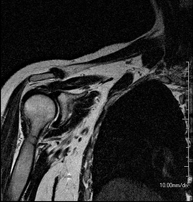

- RM Hombro

Exploración para el estudio de lesiones en tendones, músculos y articulación. Su principal utilidad reside en diagnosticar las lesiones de los tendones del manguito rotador. Tiene una duración aproximada de 20 minutos. No emplea radiación ionizante.

- Artro-RM Hombro

Exploración para el estudio de las lesiones en pequeñas estructuras anatómicas de la articulación que suelen lesionarse en pacientes que sufren luxación o inestabilidad crónica. El estudio viene precedido por una inyección de contraste en el interior de la articulación, realizada bajo control de rayos X. La duración global de los dos procedimientos es de 50 minutos.